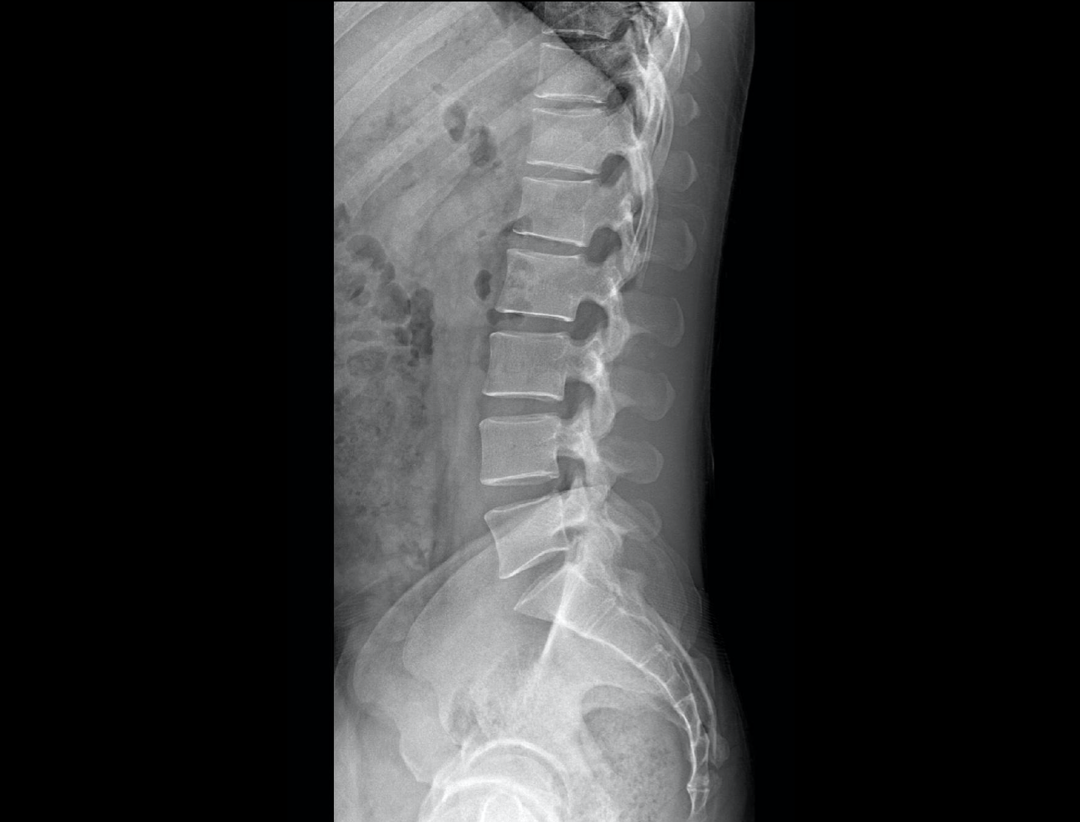

智能全景成像

全自动无尺全景拼接

支持自动立位及卧位无尺全景拼接,为骨科、整形外科提供高质量全景影像。

测量功能*

集成脊柱Cobb角及股骨颈干角测量功能,精准指导外科手术及术后评估。